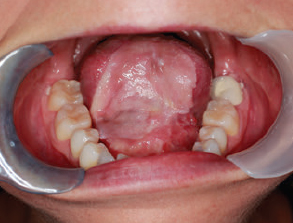

CHAPTER The oral cavity consists of the following structures: the lips, buccal mucosa, mandibular and maxillary alveolar ridge, retromolar trigone, hard palate, floor of the mouth, and anterior (oral or mobile) tongue. The pharynx is anatomically divided into the oropharynx, nasopharynx, and hypopharynx. The oropharynx is bounded by the nasopharynx superiorly, the oral cavity anteriorly, and the hypopharynx and larynx inferiorly. The main structures in the oropharynx are the base of tongue, tonsillar pillars, lateral and posterior oropharyngeal walls, and soft palate. The hypopharynx extends from the level of the hyoid bone to the lower border of the cricoid cartilage, which is congruous with the cervical esophagus below. This is a critical area that is responsible for airway protection and swallowing and speech functions. Common malignancies in the oral and pharyngeal regions include those of the lip, buccal area, floor of mouth, tongue, tonsils, hypopharynx, and larynx. The treatment of these lesions often results in surgical defects that can significantly affect the appearance and function of these vital structures. Providing basic tissue coverage for these defects without considering the functional and aesthetic outcomes is no longer acceptable in modern-day practice. Unfavorable outcomes are common in these complex reconstructions. Proper reconstruction of such defects may prevent life-threatening complications, restore essential functions such as swallowing and speech, and improve patients’ quality of life and self-image. Major head and neck surgery and free flap reconstruction pose significant perioperative risks for patients. Medical complications, not surgical complications, have been proven responsible for slow recovery, prolonged hospital stay, and poor outcomes.1 A thorough medical evaluation and consultation to the medical services before surgery are often required. Many head and neck cancer patients have a long history of tobacco and alcohol abuse. Pulmonary function should be evaluated in those with chronic obstructive pulmonary disease, and cardiovascular workup should be performed as indicated. Preoperative optimization of heart and lung functions is essential to reduce perioperative mobility and mortality. A history of peripheral vascular disease and carotid artery disease has a great impact on the flap selection, recipient vessel selection, and risks for perioperative cerebrovascular accidents. Carotid artery diseases can also be identified on head and neck CT images, which may demonstrate calcification and stenosis. Vascular specialists should be consulted when significant peripheral vascular diseases and carotid stenosis are present. Diabetes is also prevalent in this patient population and increases the risk of surgical site infection. Proper glucose control is essential. Summary Box Complications After Glossectomy and Pharyngoesophageal Reconstruction Choice of flaps is extremely important for oral and pharyngeal reconstruction. Specific defects require several considerations: • Specific flaps with appropriate thickness • Pedicle length • Ability to carry both skin and muscle • Possibility of two skin islands • Skin color match • Donor site morbidity The thickness of the flap affects not only postoperative function, but aesthetic outcomes as well. The paucity of recipient vessels may demand a flap with a long vascular pedicle to obviate vein grafting in an already-complex setting. Therefore, depending on the defects, surgical goals, and availability of recipient vessels, the choice of flap should be carefully evaluated in the preoperative planning session. The patient and family should be made fully aware of potential functional deficits, including the possibility of long-term tube feeding and tracheostomy dependency. Common donor sites such as the forearm, anterolateral thigh (ALT), abdomen, and anterior chest should be evaluated for skin quality and thickness, history of surgery or trauma, and vascular disease. Hand dominance should also be documented. A bracelet with the words “NO IV” is placed on the potential donor site arm, typically the one with the nondominant hand. Defects in the floor of mouth may vary from a small mucosal defect to a large defect involving the musculature with exposed bone. The latter often require postoperative radiotherapy, which significantly influences the methods of reconstruction. Isolated floor-of-mouth defects that do not include the suprahyoid musculature may be skin grafted or reconstructed with a facial artery musculomucosal (FAMM) flap.2,3 However, ligating and dividing the facial artery is common practice during a neck dissection. Therefore reconstruction using the FAMM flap may not be possible for patients who have had a neck dissection. When the floor-of-mouth defect extends to the upper neck, with resection of part of the suprahyoid musculature and exposure of the mandible, more extensive flap reconstruction is indicated. In high-risk patients, the pectoralis major flap is a viable option to fill the dead space in the floor of the mouth and upper neck. In young and more functional patients, however, a free flap is preferred to minimize neck deformity and maximize function. Fig. 51.1 A forearm flap can provide a thin and pliable skin for floor-of-mouth reconstruction that allows full mobility of the tongue. Fig. 51.2 When there is a large soft tissue defect in the floor of mouth, an anterolateral thigh flap with a segment of vastus lateralis muscle can provide reliable coverage and dead space filling. Fig. 51.3 (a) A bulky flap in the floor of mouth can interfere with tongue and lip function. (b) Flap thinning is possible with suction-assisted lipectomy and direct excision at the end of debulking. (c) One year later. The common problems after this type of reconstruction may include a bulky flap that limits tongue mobility and function or inadequate filling of dead space causing infection, fistula, and subsequent bone exposure that may delay adjuvant therapy and cause osteoradionecrosis. The goals are to effectively obliterate the dead space and protect the mandible from postoperative radiotherapy without unwanted bulk that may impede tongue mobility and oral function. A radial forearm flap or ulnar artery perforator (UAP) flap is ideal because they provide a thin and supple lining (Fig. 51.1). A thin ALT flap can also be used to reconstruct the floor of the mouth, with a segment of the vastus lateralis muscle used to fill the dead space (Fig. 51.2). This flap is particularly useful for large defects involving the entire suprahyoid musculature, especially after previous radiation. A shallow floor-of-mouth defect should not be covered with a bulky flap, because it may restrict tongue mobility and obliterate the lingual sulcus, causing drooling (Fig. 51.3). When the resection involves the mandibular gingiva and labial mucosa up to the vermilion border, a common mistake is to suture the flap all the way to the vermilion. This will push the lip downward and completely obliterate the labial sulcus, causing drooling, oral incompetence, and inability to eat and drink. Therefore the flap edge should be sutured to the labial tissue at the base of the labial sulcus. The remaining labial mucosal defect can be left to remucosalize or can be skin grafted. The remucosalization process takes approximately 1 week. The same principle applies to mandibular reconstruction with a fibular osteocutaneous flap when the labial mucosa defect extends to the vermilion (Fig. 51.4). Floor-of-mouth defects commonly involve the ventral tongue. A common practice is to close the tongue to itself by folding the lateral edges of the tongue ventrally and to reconstruct the floor of the mouth with a flap. This technique creates a small “snake tongue” (see Fig. 51.3a) that often causes impairment of speech and swallowing functions. A better approach is to resurface the ventral tongue and the floor of the mouth simultaneously with a thin forearm flap (Fig. 51.5) to preserve the bulk and mobility of the tongue. The tongue is a highly functional organ. A common problem after partial tongue reconstruction is the tethering of the remaining tongue, limiting tongue mobility and function. The most important goal for partial or hemiglossectomy reconstruction is, therefore, to preserve the remaining tongue function. Small defects of up to one quarter or even one third of the tongue, with minimal resection of the floor of the mouth and no communication to the neck, may be closed primarily or with a skin graft (Fig. 51.6). Resection of the floor of the mouth combined with a neck dissection creates a connection between the oral cavity and the neck along the lingual cortex of the mandible. These defects are best reconstructed with a flap to eliminate the dead space, minimizing the risk of infection and fistula formation. The remaining tongue has the ability to move intelligibly as long as it is not tethered. A bulky flap will push the remaining tongue to the side and obstruct its mobility. Therefore a thin and pliable flap should be chosen. The radial forearm flap or UAP flap is usually the first choice. Some adipose tissue in the upper forearm may be included to obliterate the submandibular dead space (Fig. 51.7). A thin ALT flap with a strip of the vastus lateralis muscle can be a good option as well. Fig. 51.4 (a) When resection of labial mucosa approaches the vermilion border, suturing the flap to the mucosal margin may obliterate the labial sulcus and push the lower lip down, causing drooling. (b) A better approach is to inset the flap to the bottom of the labial sulcus and leave the raw surface on the lip to remucosalize. This will preserve the labial sulcus and prevent drooling. Fig. 51.5 (a) After resection of the ventral tongue, closure of the remaining mobile tongue to itself may result in a “snake tongue,” with significant volume loss. (b) An alternative approach to reconstructing the ventral tongue defect is to use a thin forearm flap, part of which is also used to reconstruct the floor of the mouth. To avoid tethering of the remaining tongue, careful flap insetting is important. The length of the ventral tongue, defined as the distance from the tip of tongue to its junction with the floor of mouth and gingiva, is approximately 5 to 6 cm. The distal end of the flap is oriented toward the tip of the remaining tongue. The distal flap width, usually 6 cm, matches the ventral tongue length (Fig. 51.8). Thus one corner of the distal flap is sutured to the tip of tongue, and the other corner to the gingiva. The rest of the flap is sutured to the dorsal tongue medially and gingiva laterally. Such insetting re-creates a nice ventral sulcus and lateral gutter (Fig. 51.9). When there is no gingiva left to attach the flap to, it can be sewn to the teeth by tying the suture knots around the teeth. A single layer of interrupted 3–0 Vicryl sutures usually suffices, although some surgeons prefer horizontal mattress sutures. It is important, however, not to tie the horizontal mattress sutures too tight, which may lead to flap–mucosa edge necrosis and fistula formation. Fig. 51.6 For partial tongue defects without bone exposure or communication to the neck, full-thickness skin grafts can provide excellent coverage with preservation of tongue mobility. Fig. 51.7 (a) Partial glossectomy with neck dissection often leaves a submandibular or upper neck dead space. A conventional radial forearm flap may not have extra tissue to obliterate the dead space. (b,c) A portion of the adipofascial tissue from the upper forearm based on a proximal perforator can be included in the radial forearm for this purpose. Fig. 51.8 For hemiglossectomy reconstruction, the goal is to preserve the remaining tongue mobility without tethering. Adequate ventral sulcus and lateral gutter should be re-created with a 6 to 7 cm wide flap. The distal width of the radial forearm flap is used to re-create the ventral sulcus of the mobile tongue to prevent tethering. Fig. 51.9 With proper flap insetting, the ventral sulcus and lateral gutter of the tongue can be re-created to achieve tongue mobility. Sensory reinnervation can improve swallowing function and patient satisfaction. This can be achieved by coapting the sensory nerve of the flap to the divided lingual nerve. Sensory recovery of the flap with this technique has been well documented. The radial forearm flap, UAP flap, ALT flap, and lateral arm flap can all potentially provide sensory reinnervation.4–9 Unlike hemiglossectomy, a total or subtotal glossectomy leaves no meaningful tongue muscle. Functional outcomes are poor, and aspiration can be a serious complication necessitating a total laryngectomy in some patients. Common problems after total and subtotal glossectomy reconstruction include inadequate bulk resulting in a “funnel tongue,” inadequate vascularized tissue filling resulting in infection and fistula formation, and risks of aspiration related to resection of all floor-of-mouth musculature (Fig. 51.10). The goal of reconstruction is to create enough bulk for the neotongue. Tissue bulk is important for reconstructing large defects of the tongue for two reasons. First, it is needed to help the neotongue touch the palate to produce better speech and push food toward the hypopharynx. Second, the tissue bulk diverts saliva and food to the lateral gutters during swallowing to minimize aspiration.10 With these goals, a bulky flap should be chosen. Some muscle is also needed to obliterate the dead space in the floor of mouth and upper neck. This makes the ALT flap the ideal choice. It also has the advantages of providing sensory and motor reinnervation (Fig. 51.11). The rectus abdominis myocutaneous (RAM) is another good option. Obese men often have more adipose tissue in the abdomen than in the thighs. The opposite may be true for women. It has been suggested by some surgeons to remove the thick cutaneous portion of the flap and use the muscle only. Muscle flaps with or without skin grafts are, however, prone to atrophy and will lose significant bulk, especially after radiotherapy, resulting in a funnel shape that allows food to pour into the hypopharynx and larynx, causing aspiration. A forearm flap is usually too thin for total or subtotal glossectomy defects. Fig. 51.10 A total glossectomy with resection of all floor-of-mouth musculature leaves no tongue muscle to function and increases the risk of aspiration because of the drop of the larynx. Fig. 51.11 Both sensory and motor reinnervation is possible with the anterolateral thigh flap with a segment of the vastus lateralis muscle for total glossectomy reconstruction. (a) The lingua nerve is used for sensory reinnervation. (b) The hypoglossal nerve is used for motor reinnervation. During flap insetting, a dome of neotongue is created so that it can touch the palate easily (Fig. 51.12). Flap insetting can be difficult in a narrow jaw, particularly when no mandibular gingiva is left. It is helpful to inset the flap before revascularization while the flap is still “empty.” In addition to a funnel tongue, drop of the larynx can cause aspiration, which often occurs during a total glossectomy because the suprahyoid musculature is removed. The risk can be reduced with laryngeal suspension. Laryngeal suspension is often performed with circumhyoid sutures (0–0 Prolene) placed through drill holes in the mentum on both sides of the midline.11 The distance between the hyoid bone and the mentum is approximately 4.5 to 5 cm (Fig. 51.13). Care should be taken to avoid compression of the vascular pedicle by these suspension sutures. Fig. 51.12 Volume is necessary for total glossectomy reconstruction to reduce the risk of aspiration and improve swallowing and speech functions. Functional muscle transfer has been successfully used to restore upper extremity functions and for facial reanimation. However, it is rarely used in tongue reconstruction and produces uncertain results. My experience and that of others12,13 have shown minimal muscle movements after a functional muscle flap such as a gracilis flap or ALT flap with the vastus lateralis muscle by coapting the motor nerve of the flap to the hypoglossal nerve. My current approach is to use the ALT flap with vastus lateralis muscle with both sensory and motor reinnervation, because these additional procedures are easy to perform and add little extra time. Without postoperative radiotherapy, reinnervation of the muscle may prevent muscle atrophy. Postoperative radiotherapy, however, may destroy the motor end plates before reinnervation occurs. As with partial glossectomy reconstruction, sensory reinnervation may improve swallowing functions and patient satisfaction.8 Fig. 51.13 After a total glossectomy, static laryngeal elevation can be achieved with circumhyoid sutures to suspend the larynx to the mandible. The difficulties of postlaryngopharyngectomy reconstruction are mainly the results of previous radiotherapy and neck surgery. This increases the risk for delayed wound healing, fistula formation, infection, carotid artery rupture, lack of recipient vessels, a combined pharyngoesophageal and neck skin defect, and tracheoesophageal puncture (TEP) complications. Functional outcomes such as speech and swallowing can be disappointing as well. In addition to being nonvocal after a total laryngopharyngectomy, postreconstruction complications such as pharyngocutaneous fistulas and anastomotic strictures may render patients dependent on tube feeding. Radiotherapy has become the primary treatment for early stages of squamous cell carcinoma in the larynx and hypopharynx. Therefore the majority of laryngopharyngectomy cases are recurrent cancers that have failed radiotherapy and, in some cases, previous neck dissection. These defects are among the most difficult to repair in head and neck reconstruction. The reconstructive goals are to provide alimentary tract continuity, protect great vessels, maximize TEP speech and swallowing functions, reduce the risk of fistula formation, and minimize neck deformity and donor site morbidity. The choice of flaps for pharyngoesophageal reconstruction is important. The flap has a great impact on defect coverage, restoration of speech and swallowing functions, simultaneous neck resurfacing and tracheostoma reconstruction, and donor site morbidity. Commonly used flaps include the ALT flap, jejunal flap, radial forearm flap, and pectoralis major myocutaneous flap.14–20 The pectoralis flap gained popularity in the early 1980s but is used less now because of advances in free flap reconstruction. In general, enteric flaps heal fast but tracheoesophageal (TE) speech is poor and donor site morbidity is higher. Conversely, fasciocutaneous flaps heal slower but TE speech is superior and donor site morbidity is minor.21,22 ALT flaps have largely replaced jejunal and radial forearm flaps in the last decade. If the ALT flap is unavailable because of a lack of perforators or is deemed too bulky, a radial forearm flap or ulnar artery perforator flap is the next choice. In otherwise healthy patients with a circumferential defect, the jejunal flap is another good choice. Contraindications of the jejunal flap include significant comorbid diseases, obesity, and a history of abdominal or gastrointestinal surgeries. The pectoralis major flap can be used for partial defects in male patients, for salvage after failed free flap reconstruction, or in very high-risk patients who cannot tolerate a free flap surgery. The advantage of ALT flaps over forearm flaps is that an ample amount of fascia, the vastus lateralis muscle, and a large second skin paddle can be included for better coverage of the soft tissue defect in the neck, thus potentially reducing the risk of fistula formation. The flap is usually partially inset before revascularization. Recipient vessel choices include the branches of the external carotid artery and facial vein. In a previously radiated and operated neck, using the transverse cervical vessels may avoid difficult and risky dissection around the carotid artery.23,24 Before closure of the neck incision, the neck is slightly flexed with the head in a neutral position. This repositioning may cause kinking or twisting of the vascular pedicle. Therefore the vascular pedicle should be carefully inspected again before closing the neck incision. The second skin paddle is then turned outward to resurface the neck, to reconstruct the tracheal defect, or for flap monitoring. To monitor a buried flap without an external skin island, I prefer externalizing a small skin island based on a second cutaneous perforator or externalizing a small amount of the vastus lateralis muscle based on a muscular branch.25 This technique is highly reliable, because three-dimensional assessment of the entire skin or muscle is possible. This second skin island or muscle is then brought out through the neck incision and covered with petroleum jelly–impregnated gauze to prevent desiccation. A 2–0 silk tie may be placed around the perforator at the skin level so that the pedicle can be easily tied when it is time to remove the monitor segment. The monitor is removed 5 to 7 days later, before the patient is discharged from the hospital. Alternatively, a handheld Doppler device can be used to monitor the perforator or the main vascular pedicle through the neck skin. The Flow Coupler (Synovis) provides an additional method of flap monitoring. With the jejunal flap, a 3 to 4 cm long monitor segment is created from the remaining jejunum based on branches of the pedicle vessels. Both ends of the bowel segment are left open to avoid distention. At the time of neck closure, the tracheostoma is sutured to the surrounding neck and anterior chest skin, and a No. 8 Shiley tracheostomy tube is placed in the tracheostoma and secured to the chest skin. Fig. 51.14 During flap insetting for circumferential pharyngoesophageal reconstruction, positioning the perforators of the anterolateral thigh flap posteriorly may cause perforator compression against the vertebrae and flap failure. Fig. 51.15 The longitudinal seam of the tubed anterolateral thigh flap is positioned more posteriorly with the perforators in the anterior location to avoid compression and kinking. When the ALT flap is tubed to reconstruct a circumferential defect, the perforators need to be carefully positioned. If they are positioned posteriorly against the prevertebral fascia, the swelling of the flap can easily compress the perforators against the hard surface of the vertebrae, causing flap failure (Fig. 51.14). During flap insetting, the proximal anastomosis between the flap and the base of tongue is usually performed first. The longitudinal seam is positioned posterolaterally at the 4 or 8 o’clock position for easy suturing of the T junction. It can be positioned at 6 o’clock if the flap is tubed first. Anastomosis starts with two corner sutures at the 3 and 9 o’clock positions. The posterior wall is then completed, followed by the anterior wall. The tubed flap is slightly twisted so that the longitudinal seam at the distal anastomosis is facing posteriorly at the 6 o’clock position. Such positioning of the tubed flap places the perforator vessels anteriorly between the 11 and 1 o’clock positions to avoid compression of the perforators against the prevertebral fascia. The entire vascular pedicle can be placed anteriorly across the flap to avoid sharp kinking (Fig. 51.15). Anastomotic strictures can result from a circular scar formation, inadequate diameter, a thick flap, postoperative radiation, or fistula. To obtain a sufficient lumen, a flap width of 9.4 cm is required to achieve a 3 cm diameter (3π) for the tubed neopharynx or esophagus.19 For partial defects, the width of the flap is calculated by subtracting the width of the remaining pharyngeal mucosa from 9.4 cm. The flap can be thinned as needed by direct excision of subcutaneous fat at the periphery of the flap. Ample subcutaneous tissue should be left around the cutaneous perforators, and 2 to 3 mm of subcutaneous tissue is left on the dermis to protect the subdermal plexus. The anterior wall of the cervical esophagus is split longitudinally for approximately 1.5 cm to spatulate the distal anastomosis (Fig. 51.16). This is important to enlarge the distal anastomosis and minimize the risk of ring stricture. On the flap side, a triangular lip is created and inserted into the longitudinal split of the esophagus to complete the spatulation (Fig. 51.17). A Montgomery salivary bypass tube with a diameter of 14 mm can be placed inside the tubed flap during circumferential reconstruction in some patients. This technique may further reduce stricture and fistula formation. The indications for the use of the Montgomery tube include a thick flap, difficult flap insetting, very low location of the transected cervical esophageal end, small cervical esophagus, or poor tissue quality because of radiation injury. The tube is inserted through the mouth before the longitudinal seam of the flap is completed. The proximal flange of the bypass tube is placed above the proximal anastomosis, and the distal end is placed in the esophagus below the distal anastomosis. A 1–0 Prolene suture is attached to the flange of the tube, brought out through the mouth, and taped to the cheek to prevent distal migration and facilitate easy removal of the tube. A 10 Fr red rubber catheter is placed over the Prolene suture to protect the oral commissure (Fig. 51.18). Fig. 51.16 To spatulate the distal anastomosis to minimize ring strictures, the anterior cervical esophagus is incised longitudinally for approximately 1.5 cm. Fig. 51.17 A triangular lip of flap is created to be inset to the longitudinal opening of the cervical esophagus to complete the spatulation. Fig. 51.18 For some patients, a Montgomery salivary bypass tube can be placed in the reconstructed esophagus to minimize the risks of leakage and stenosis. (a) A Prolene suture is placed on the flange of the tube and taped to the cheek. (b) A small red rubber catheter is placed over the Prolene suture to prevent the suture cutting through the oral commissure. If a feeding tube has not yet been placed, a Dobbhoff feeding tube is placed through the nose and flap or inside the Montgomery salivary bypass tube, and through the cervical esophagus to the stomach. The Montgomery tube is usually removed 4 to 6 weeks after reconstruction. This can be done in the clinic without sedation by pulling out the previously placed Prolene suture. In my experience, pharyngocutaneous fistulas occur in 6% of patients.19,20 Fistula rates are similar in partial and circumferential reconstructions. Pharyngocutaneous fistulas occur more commonly at the distal anastomosis than at the proximal anastomosis, most likely related to the thin, less well-vascularized cervical esophagus compared with the base of the tongue. In fact, proximal fistulas are rare with the ALT flap unless there is a dehiscence from poor tissue quality. It has been speculated that the longitudinal seam of a tubed fasciocutaneous flap or two longitudinal suture lines in a partial defect might have contributed to a higher incidence of fistula formation with the radial forearm flap. However, in my experience, the fistula rate with the ALT flap is no higher than with the jejunal flap, and no fistulas have occurred through the longitudinal suture lines. Fistulas usually develop between 1 and 4 weeks postoperatively and manifest as leakage of saliva or liquids or, in some patients, as a neck infection. Therefore any neck infection or abscess that occurs after a pharyngoesophageal reconstruction should raise suspicion for anastomotic leakage. Risk factors for fistula formation include improper suturing techniques, poor tissue quality at the anastomosis site, previous radiotherapy, lack of well-vascularized tissue protection of the anastomosis, and turbulent postoperative course. At the time of surgery, any questionable tissue in the proximal pharynx and cervical esophagus should be trimmed until well-vascularized tissue is seen. Although a watertight seal using a horizontal mattress suturing technique is advocated by some, I believe that such tight horizontal mattress suturing may actually cause necrosis of the mucosal edges and thus increase the risk for fistula. I prefer single-layer, simple interrupted 3–0 Vicryl sutures for flap insetting, taking relatively big bites, inverting the skin and mucosal edges into the lumen, spacing each suture 5 to 7 mm apart, and avoiding tight knots. To further protect the suture lines, a second layer of fascial closure is recommended. Fig. 51.19 A novice mistake is to deepithelialize a strip of skin and externalize a portion of the flap for neck coverage. This results in a high fistula rate. Once a leakage occurred in this patient, the de-epithelialized portion reepithelialized quickly because of the lack of contact inhibition, resulting in a nonhealing fistula. During ALT flap harvesting, a wider amount of fascia than skin is included in the flap. When making the anterior incision, the fascial incision is made 1 to 2 cm more medially than the skin incision. Likewise, an additional 1 to 2 cm of fascia is recruited posteriorly. After completion of flap insetting, the extra fascia of the flap is wrapped around the flap to reinforce the suture lines and cover the anastomoses. Placement of the Montgomery salivary bypass tube inside the flap may also reduce the risk of fistula in high-risk patients by protecting the anastomosis from constantly soaking in saliva. If neck resurfacing is needed but only one cutaneous perforator remains, an attempt might be made to externalize a portion of the distal flap by deepithelializing a strip of skin around the distal anastomosis (Fig. 51.19). This, however, results in a high fistula rate.19 Even with a minor leakage, the deepithelialized portion will reepithelialize, causing a nonhealing fistula. The timing for resuming an oral diet after surgery may also have an effect on fistula formation. The radial forearm flap has a reputation of having high fistula rates and having delayed fistulas that occur 4 to 5 weeks after surgery.14,15 A fasciocutaneous flap does not heal as quickly as a jejunal flap once it is immersed in saliva 24 hours a day. This may explain the high incidence of delayed fistula formation. In fact, the anastomosis may experience secondary healing, which could take 4 to 6 weeks. If an oral diet is started early, for instance 7 days after surgery, as with the jejunal flap, fistulas will likely develop with the unhealed fasciocutaneous flap. After fasciocutaneous flap reconstruction, I routinely delay oral intake for 2 weeks in nonirradiated patients and for 4 to 6 weeks in patients who have undergone radiotherapy. Before oral intake, a modified barium swallowing study is performed. If no leaks or fistulas are identified, a liquid diet is started and then advanced to a regular diet as tolerated. In the presence of a leak, oral intake is delayed, and the modified barium swallowing study is repeated in two weeks. Most leaks heal within 2 weeks. In a previously irradiated patient, the tracheostoma is at risk for necrosis and dehiscence. This could be the result of an ischemic tracheostoma itself or ischemic neck and chest skin or tight closure. The blood supply to the trachea arises laterally. Extensive lateral dissection on both sides to skeletonize the trachea should be avoided. When the tracheal stoma is short, excessive undermining of the previously irradiated anterior chest skin to reach a low tracheostoma under tension can easily cause skin necrosis, because it is compressed over the clavicular heads. An alternative approach to mature the anterior wall of the tracheostoma is to use a pedicle internal mammary artery perforator (IMAP) flap.26 Questionable neck skin around the tracheostoma should be débrided, and well-vascularized skin from the flap should be used instead. Full-thickness skin grafting over the vastus lateralis muscle to mature the posterior tracheostoma and anterior neck can provide very stable coverage. Another common problem with the tracheostoma is partial obstruction related to a bulky second skin paddle for external coverage. The skin paddle should be thinned as much as possible at the time of reconstruction. Alternatively, muscle and skin grafting can provide excellent results. When a Shiley tube is placed in the tracheostoma with a bulky skin paddle, the flange of the Shiley tube can cause compression and necrosis of the skin around the tracheostoma. To avoid this, the superior flange of the Shiley tube is trimmed and a longer tube should be used (Fig. 51.20). The flap can also be thinned using suction-assisted lipectomy several months after surgery; this method works extremely well. For tracheoesophageal voice rehabilitation, patients commonly wear a hands-free stoma button. This button needs to sit inside the tracheostoma securely. Ideally, the tracheostoma should have a circumferential flange to secure the voice button without the bowstring of the neighboring sternocleidomastoid (SCM) muscles. This can be achieved by dividing the medial edges of the SCM before neck closure and maturing the tracheostoma using a semivertical mattress suturing technique to create a flange (Fig. 51.21). A frozen or woody neck, defined as severe fibrosis in the neck without tissue planes, is the result of neck surgery (such as neck dissection) combined with radiotherapy.24 Long-standing pharyngocutaneous fistulas usually result in the worst cases of frozen neck. There are three major problems associated with managing a frozen neck during reconstruction: 1. Risk of carotid artery rupture 2. Lack of recipient vessels 3. Concomitant neck skin or tracheal defects